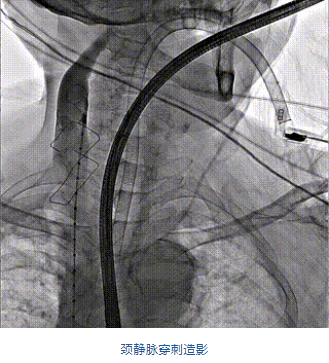

團隊前期經過多次討論,制定了周密的手術策略和預案。由于患者已是近九旬的超高齡老人,傳統外科開胸手術風險極高,純介入經血管三尖瓣替換能夠明顯減少創傷。術中陳茂及馮沅教授結合體表定位在造影指示下精準穿刺右側頸靜脈并預置兩把血管縫合器。成功建立經皮血管入路后在食道超聲和DSA的引導下順利完成人工瓣膜植入,術后超聲和造影顯示人工三尖瓣同軸性良好,瓣架固定牢靠,無反流和瓣周漏,平均跨瓣壓差降為1mmHg。術畢收緊預置的血管縫合器縫線完成止血,縫合效果滿意,在手術室即刻拔除氣管插管。